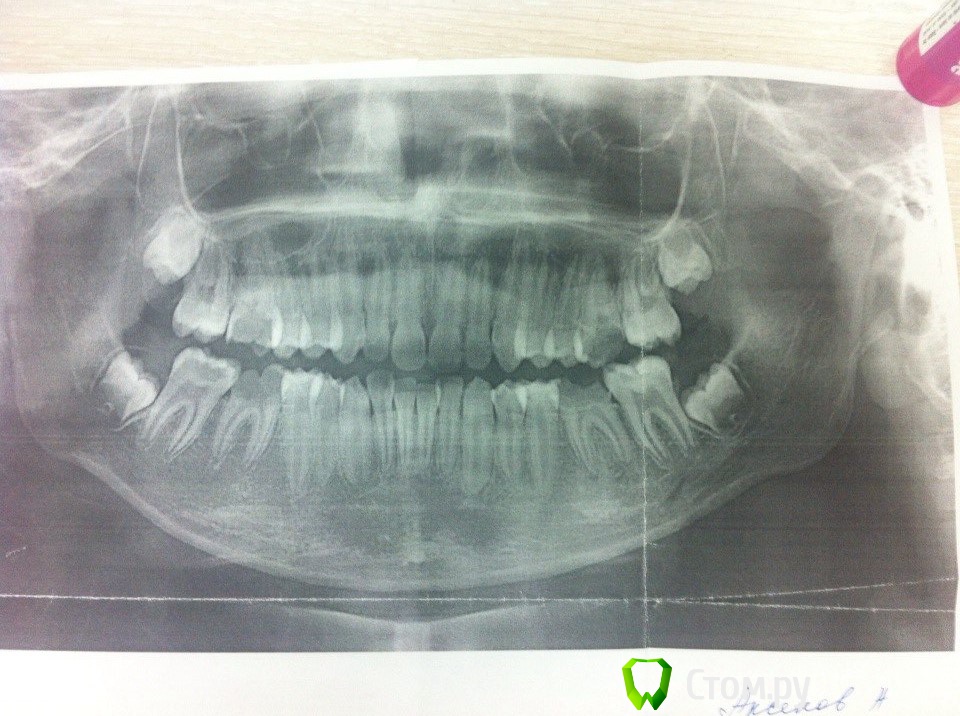

cor Опубликовано 22 ноября, 2014 Поделиться Опубликовано 22 ноября, 2014 Доброго времени суток, прошу совета.Подошла сегодня наш детский стоматолог и попросила взять на лечение пациента-ребёнка(я просто взрослый терапевт). Подскажите тактику лечения, и как вообще вести такие случаи, потому что на приём мне его записали (вроде на вторник), и родителям надо что то сказать, а я в "детстве" ни в зуб ногой. И нет, я не знаю, но догадываюсь почему она сама лечить не хочет. Пациент, 12 лет. Со слов врача - "плохая гигиена, половина зубов пульпитные". 26 зуб уже удалили. На очереди, без скорого лечения, остальные шестёрки и семёрки. Диагнозы со слов доктора - 16, 36,46 - периодонтит, 37,47 - пульпит.Пытаюсь найти детского терапевта, конечно, но вдруг придётся что то делать(опять откажутся лечить). не оставлять же парня без зубов в 12 лет. Есть только фото печатного ОПТГ, до удаления 26. Заранее благодарю. Ссылка на комментарий

Доктор Саша Опубликовано 30 ноября, 2014 Поделиться Опубликовано 30 ноября, 2014 не увидел периодонтитов в 6.. пульпиты в 7 ( если есть ) с несформир корнями...В 6 эндо полноценное с коффером + культи из СИЦ + врем метал коронки , может и на 7 тоже до 18 лет Ссылка на комментарий

CRAZYDUCK Опубликовано 30 ноября, 2014 Поделиться Опубликовано 30 ноября, 2014 по орто - да не видно , но там еще же доктор смотрела - сказала про периодонтиты, может сделала прицельные , раз уверенность такая в периодонтитах Ссылка на комментарий

Доктор Саша Опубликовано 2 декабря, 2014 Поделиться Опубликовано 2 декабря, 2014 по орто - да не видно , но там еще же доктор смотрела - сказала про периодонтиты, может сделала прицельные , раз уверенность такая в периодонтитахМожет быть... Имеет значение степень разрушения под десну. Глубоко если - в тазик, нет - лечим. + врем коронки из того же набора 3М Ссылка на комментарий